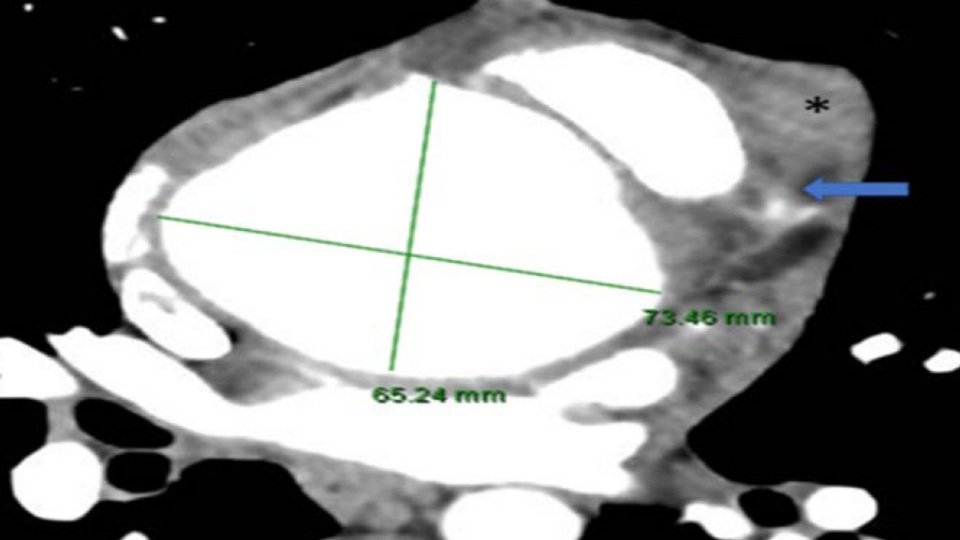

Thoracolumbar spine and pelvis computed tomography (CT) performed and showed multiple lytic lesions in the thoracic and lumbar spine involving both vertebral bodies and posterior elements of the spine. Bilateral pelvic bones multifocal lytic lesions with pathological fractures are seen (Figure 2).

Magnetic resonance imaging (MRI) of the spine showed multiple expansile osteolytic lesions along the axial skeleton, including the thoracic and lumbar vertebrae, ribs, and pelvic bones. A large expansile lesion involving the posterior neural element of the (T3) vertebra with intraspinal epidural soft tissue component compressing the posterior aspect of the upper thoracic cord was noted. Another expansile lesion, as seen in the (T6) and (T7) vertebra with a large soft tissue component totally occluding the neural canal, was noted (Figure 3).